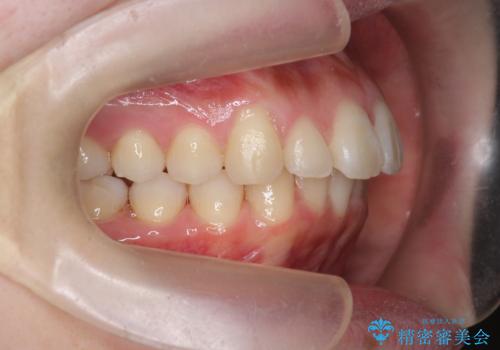

マウスピースで出っ歯感の改善

- 上の前歯が出ている感じを治したい、と矯正治療を希望され来院されました。

上顎歯列の突出感を改善すべくIPRを行い、下顎歯列を小さくすることで前歯の角度を大きく是正します、。

下顎歯列は元々前歯が1本少なく小さなアーチでしたが、下顎に合わせ上顎歯列もIPRを行い小さくすることで出っ歯感を大きく改善することが出来ました。